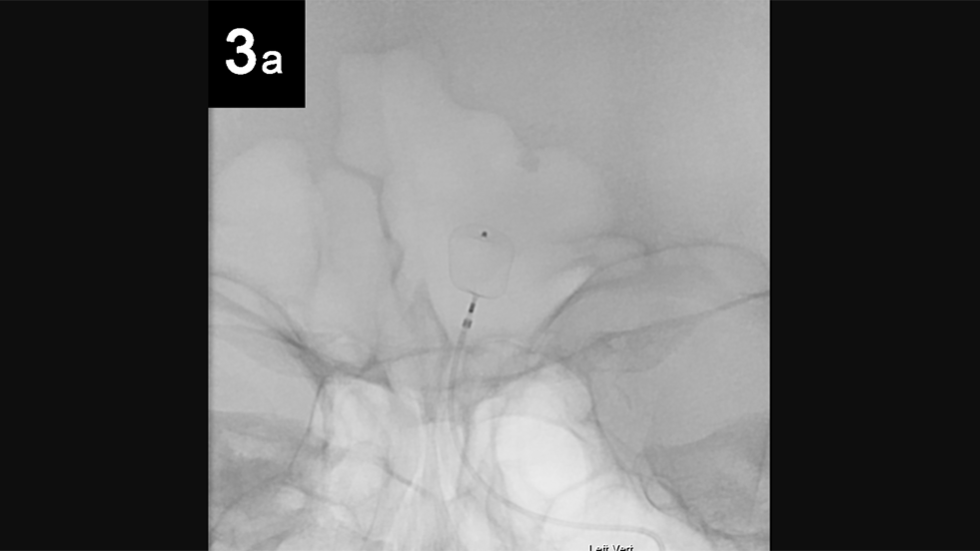

Intrasaccular: 3a

3 of 6